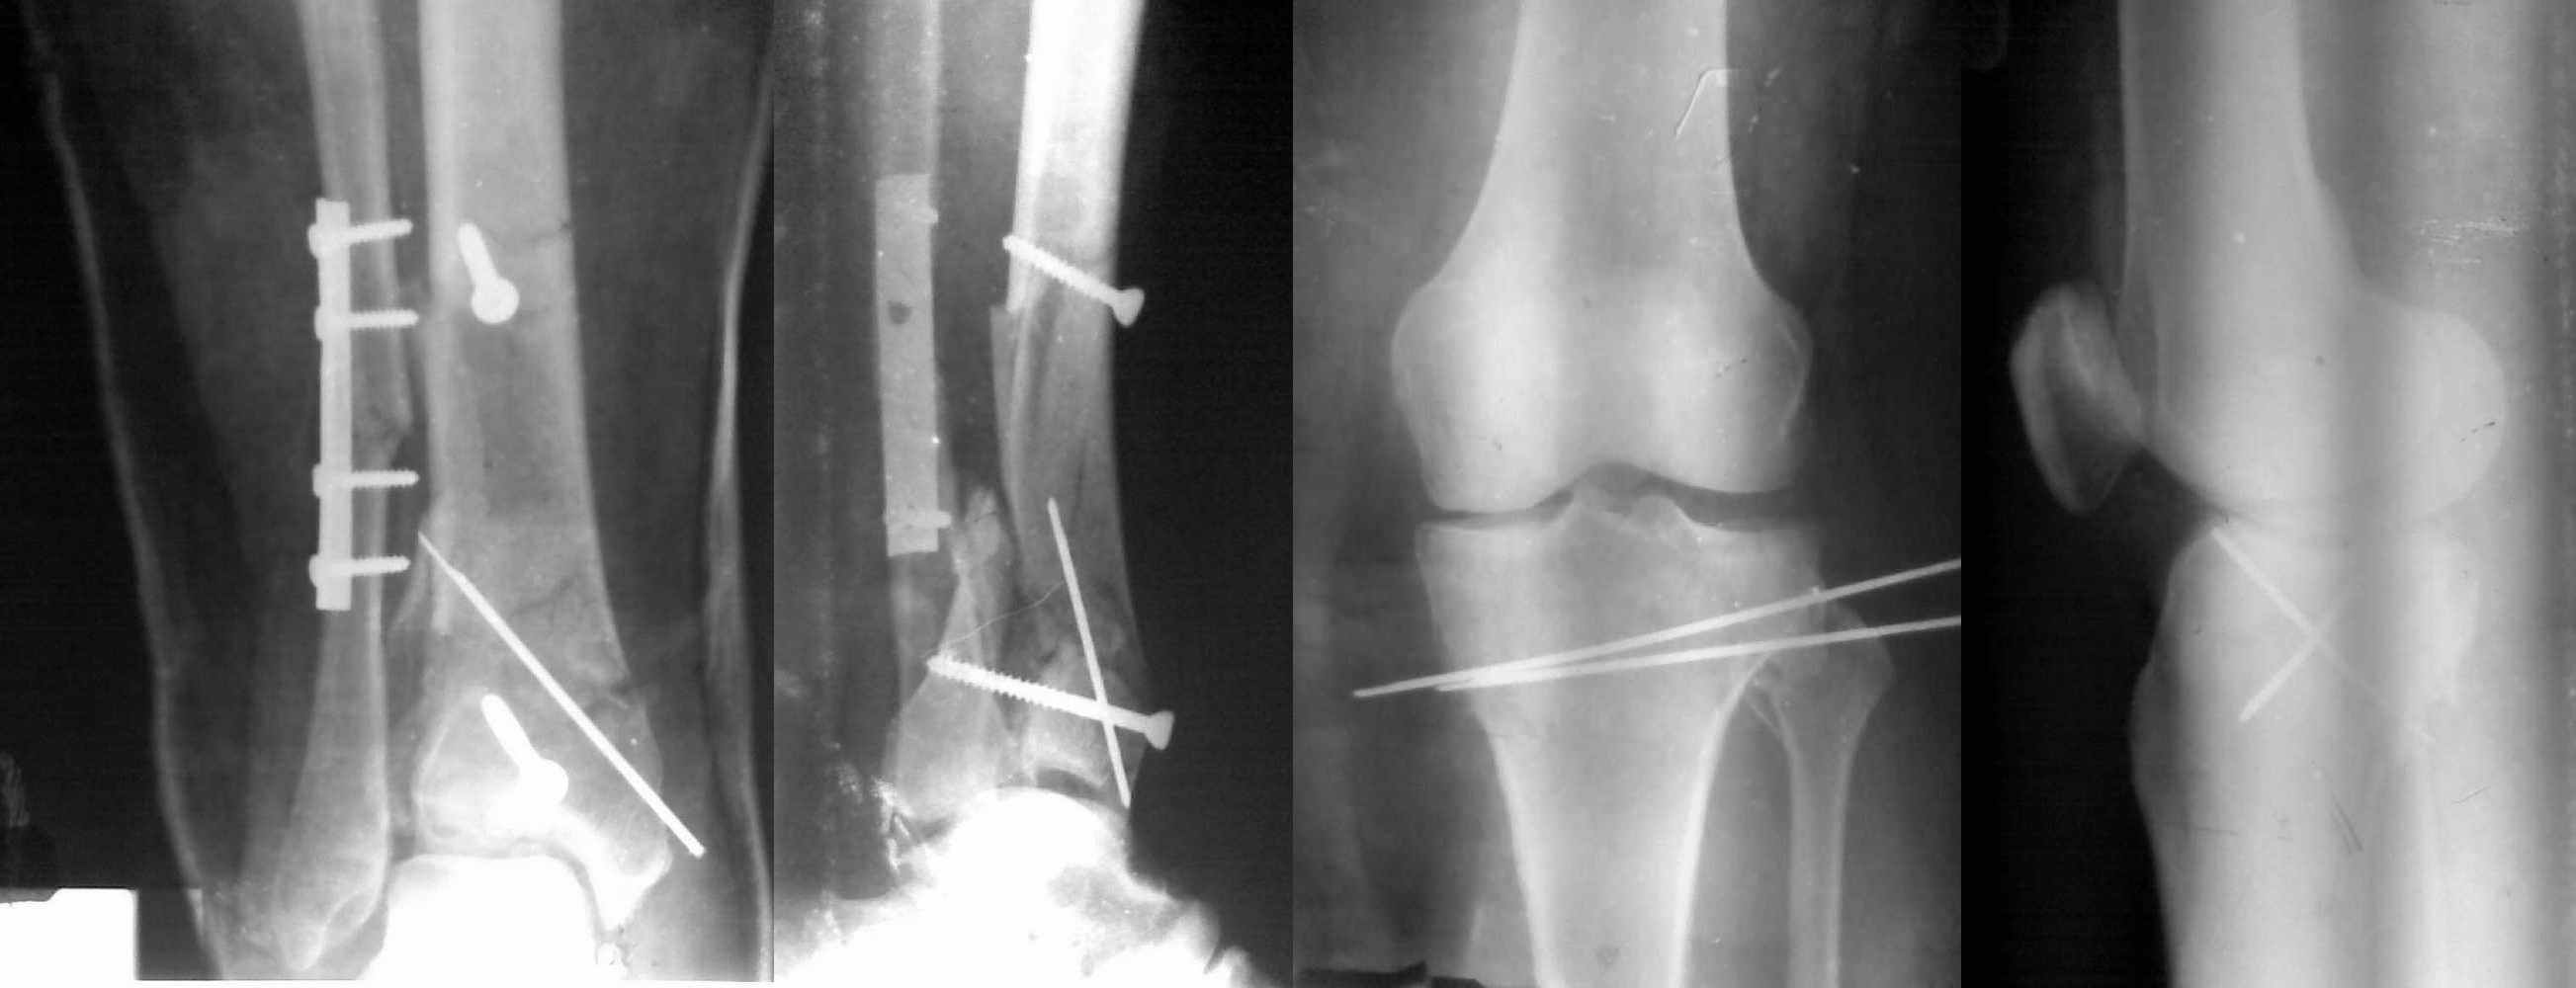

Снимки до и после закрытой репозиции

Пациентки прооперирована, результат чего на снимках. Выполнена открытая репозиция костей правой голени, синтез малоберцевой пластиной, б/берцевой винтами, имеющиеся фиксаторы не подходили, было принято решение репонировать отломки, синтез винтами, гипсовая повязка.

В данный момент локально отёк тыла стопы незначительный, двигательня функция сохранена, ограничена болевым синдромом. Пульсация артерий ослаблена, соответствует левой ноге. Рана - в области границы с пузырём область некроза 2.5*2 см, сухой, не увеличивается, под ним чувствительность сохранена. Чувствительность по всей поверхности кожи в норме, гипоестезия пальцев, при чём варьирует от нормальной, до почти анестезии в течении дня.

Репозиция внутрисуставных переломов неудовлетворительная и не адекватна.

сценарий и для перелома наружного мыщелка б.б.- передний фрагмент стоит на месте, а задний не репонирован - в таком положении оставлять фрагменты нельзя, суставная поверхность должна быть реконструирована.

В лечении переломов пилона восстановление длины малоберцовой является индикатором и ориентиром для успешного лечения. Первый этап восстановления по длине не удался, малоберцовая остается короткой, и репозиция суставной поверхности осталась неудовлетворительной. Длина передней колонны не восстановлена, а в дистальном фрагменте имеется флексия. Оставлена без внимания потеря кости в метафизе. Шурупы 4.5 мм будут выступать после спадения отека, и возможно будут причиной мягкотканого осложнения в гипсе.